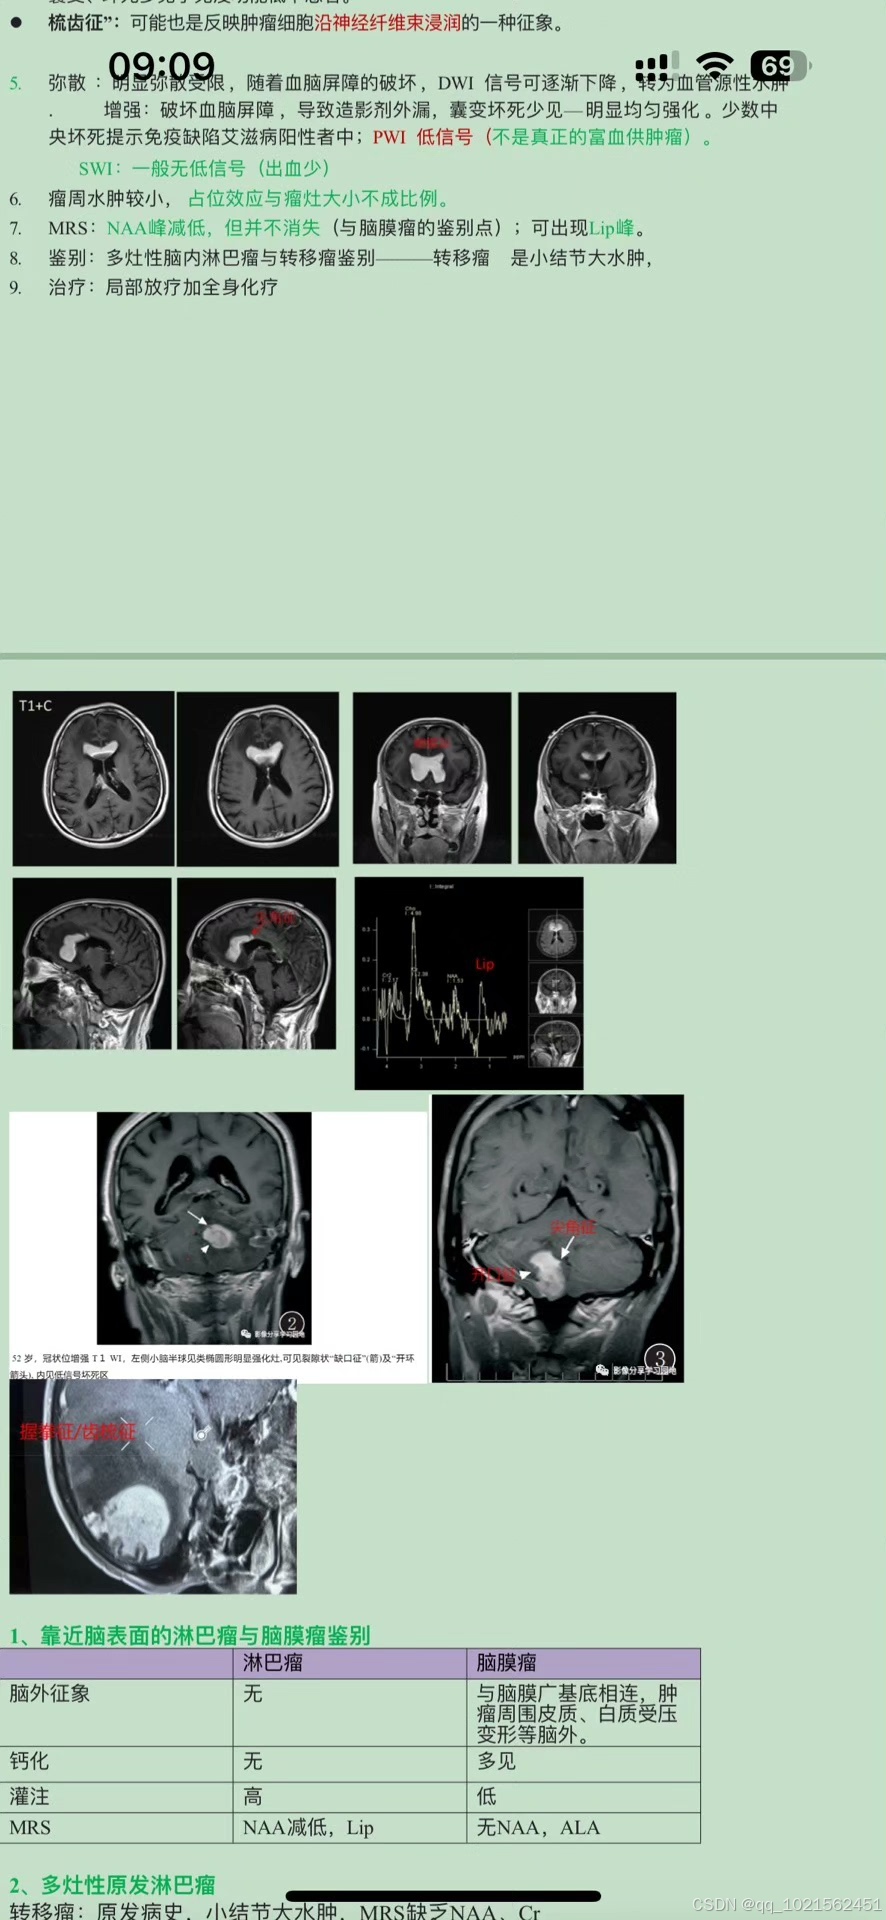

规培结业考试已通过,现分享自己花了大量时间和精力根据考点做的重点笔记,里面包含实际病例影像图片帮助记忆,横向和纵向鉴别诊断表格等,适合看不下去教材,没时间梳理和总结重点的朋友。

笔记来源:最初是为了研究生复试,收集了各个院校的笔试大题和面试专业题题干,然后根据教材的知识点,辅以各种其他书籍、专业公众号整理的答案,这里面不是单纯知识点的罗列,而是结合了实际考题进行了有逻辑的梳理,里面有很多鉴别诊断的表格,还有思维导图。最后背了自己整理的资料,考研面试成绩第一。后面在规培的过程中根据规培大纲和日常写报告的经验,又如法炮制,进一步完善了这份笔记,在规培结业考试的时候就直接省去了看教材这个过程,为我大大提升了效率,缩短了复习时间!!!!